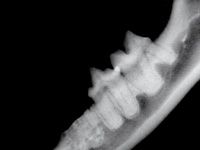

Photo 2: The right mandibular fourth premolar, tooth 408 (white arrow), has a subtle crown lucency but an intact periodontal ligament space surrounding the roots consistent with Type 1 tooth resorption. The third premolar, tooth 407 (yellow arrow), has more pronounced crown lucency and no discernable periodontal ligament space surrounding the roots, which is typical of Type 2 tooth resorption.

Photo 3: The left mandibular third premolar, tooth 307 (arrow), demonstrates both types of tooth resorption. The mesial root has a periodontal ligament space consistent with Type 1 tooth resorption. The distal root has an indistinguishable periodontal ligament space and resembles Type 2 resorption.

Type 2 (Photos 2 and 3) tooth resorption is generally thought to start at the apical half of the root. Crown involvement is generally not noted until late in the resorption process. The hallmark of Type 2 resorption is the lack of radiographic evidence of a periodontal ligament space surrounding the root.